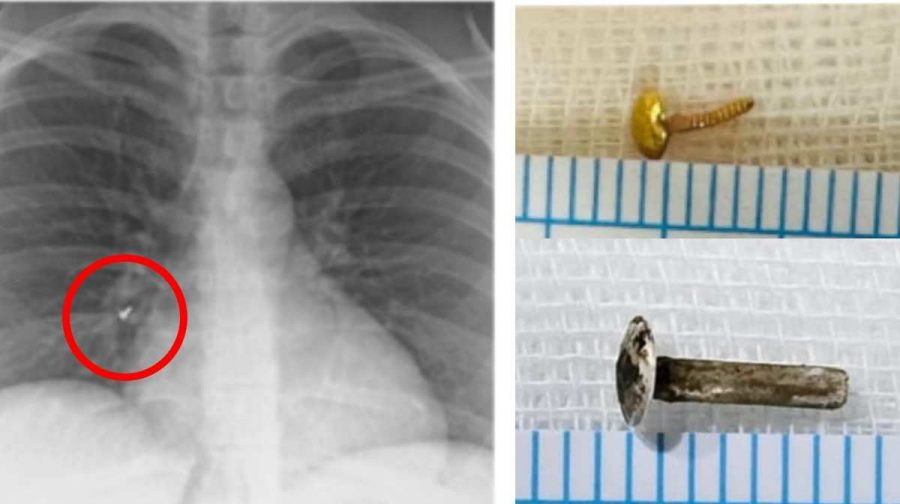

രണ്ടാഴ്ചക്കിടെ മൂന്ന് സ്ത്രീകളുടെ ശ്വാസകോശത്തില്‍ നിന്നാണ് മൂക്കുത്തിയുടെ ആണി കണ്ടെടുത്തത്.  ശ്വാസകോശത്തില്‍ ആണികൂടുങ്ങിയെന്ന കാര്യം യുവതികള്‍ അറിഞ്ഞിരുന്നില്ല. വിദേശ യാത്രക്കുള്ള വീസ നടപടികളുടെ ഭാഗമായി നടത്തിയ പരിശോധനയിലാണ് രണ്ട് സ്ത്രീകളുടെ ശ്വാസകോശത്തില്‍ മൂക്കുത്തിയുടെ അകപ്പെട്ടത് കണ്ടെത്തിയത്.  ആരോഗ്യ പരിശോധനയുടെ ഭാഗമായി എക്സ്റേ എടുത്തപ്പോഴാണ് 52 കാരിയായ മറ്റൊരു സ്ത്രീയുടെ ശ്വാസകോശത്തില്‍ ആണി കണ്ടെത്തിയത്.

31കാരിയായ സ്ത്രീയുടെ മൂക്കുത്തിയുടെ ആണി കാണാതായിട്ട് രണ്ട് വര്‍ഷത്തോളമായി. ശ്വാസകോശത്തിന്‍റെ വലതു ഭാഗത്ത് അടിവശത്തായി തറഞ്ഞു കിടക്കുകയായിരുന്നു ഇത്. 44 കാരിയുടെ ശ്വാസകോശത്തില്‍ കണ്ടെത്തിയ വെള്ളി മൂക്കുത്തിയുടെ ആണി നഷ്ടപ്പെട്ടത് ആറുമാസം മുന്‍പാണ്.

ആണി ശ്വാസകോശത്തില്‍ അകപ്പെട്ടതിന് ശേഷം മൂവര്‍ക്കും ചെറിയ തോതിലുള്ള ചുമയല്ലാതെ മറ്റ് കാര്യമായ ആരോഗ്യപ്രശ്നങ്ങളൊന്നുമുണ്ടായിരുന്നില്ല. മൂക്കുത്തി ഉറപ്പിച്ച് മുറുക്കിയിട്ടില്ലെങ്കലില്‍ ഉറക്കത്തിലടക്കം  ആണിയും അനുബന്ധ ഭാഗങ്ങളും  ശ്വാസകോശത്തിൽ എത്താനുള്ള സാധ്യതയുണ്ട്.